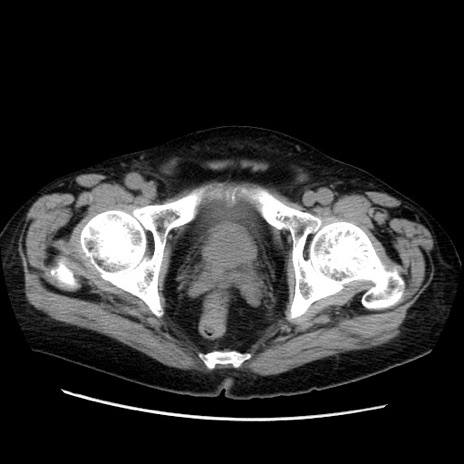

症例21(横断像)

【症例】70歳代男性

【主訴】腹痛

【現病歴】肝硬変・肝細胞癌にてかかりつけの方。約9時間前に食後より腹痛出現。症状が徐々に増悪し、嘔吐出現したため来院。

【既往歴】肝硬変、肝細胞癌(RFA、TACE後)

【身体所見】意識清明、表情苦悶様、BT 36℃、BP 129/78mmHg、P 88bpm、SpO2 97%(RA)、右上腹部から心窩部にかけて圧痛あり、反跳痛なし、筋性防御あり。

【データ】WBC 5800、CRP 0.16